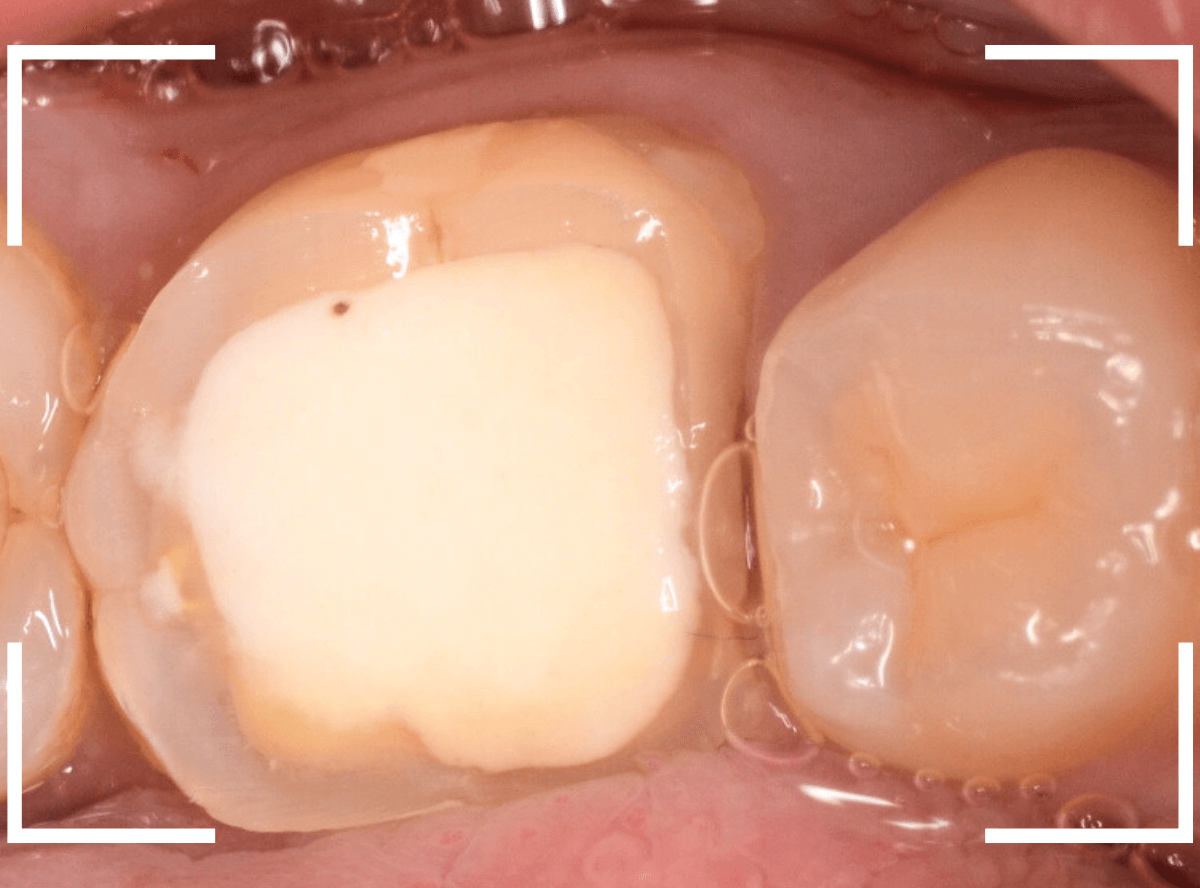

歯の裏側の大きな虫歯を処置した方です。

白いセメントで埋まっている部分が虫歯の処置をした部分なのですが、虫歯が大きく、歯の2/3くらい削る必要がありました。

しばらく経過観察したのですが、特に症状もなかったとの事でしたので、歯の形をトリミングして、型どりにはいる段階です。

悩むところですが、なるべく歯の白い部分を残すつめもの(インレー)では、長持ちするのが難しいかと考えました。

患者さんと相談の上、審美性の高い、さし歯、オールジルコニア・クラウンでしっかり覆うことになりました。

さし歯を製作するために、歯全体を大きく削り、色合わせ、型どりをします。